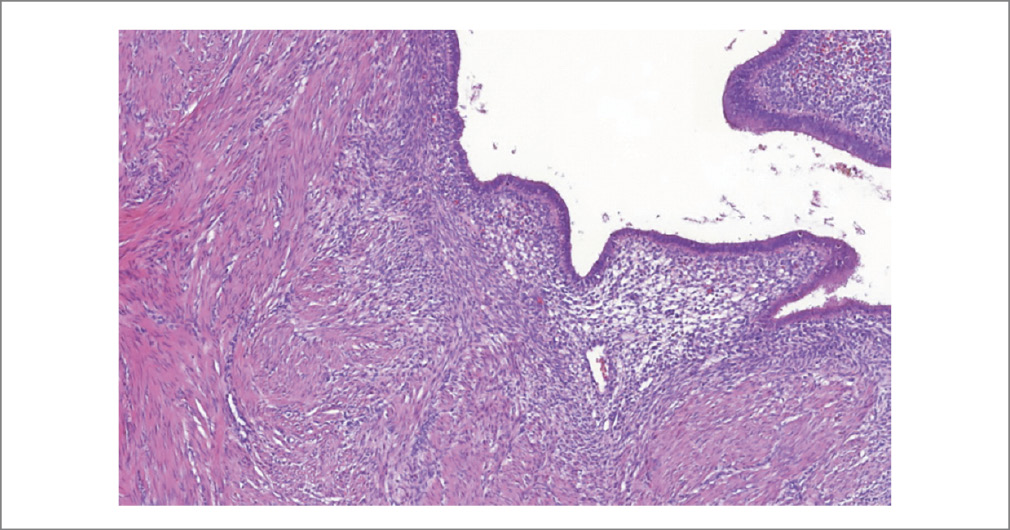

Рис. 4. Железы эндометрия в миометрии. Диагноз: аденомиоз. Окраска гематоксилин-эозином. ×100.

Fig. 4. Endometrial glands in the myometrium. Diagnosis: adenomyosis. Hematoxylin-eosin staining. ×100.

Рис. 5. Железы эндометрия, цитогенная строма. Окраска гематоксилин-эозином. ×80.

Fig. 5. Endometrial glands, cytogenous stroma. Hematoxylin-eosin staining. ×80.

Результат патоморфологического исследования биопсийного материала (серо-розовая ткань плотно-эластичной консистенции, на разрезе белесоватого цвета, слоистого вида) представлен фрагментами новообразованной ткани, хаотично располагающимися мышечными волокнами с неравномерным разрастанием соединительной ткани, с фокусами соединительной ткани с участками, представленными эндометриоидными железами и стромой, по периферии – макрофаги, фагоцитирующие гемосидерин (рис. 3). При иммуногистохимическом исследовании выявлена умеренно выраженная экспрессия рецепторов эстрогена и прогестерона в клетках и железах эндометрия (рис. 4–8).